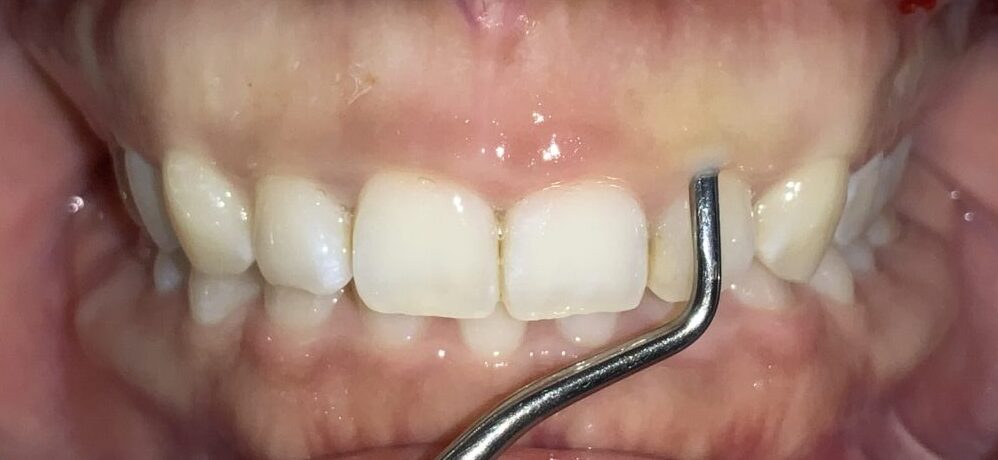

反対側の歯も調べてみます。前歯の形はとても大切ですから、慎重に検査を進めます。

この歯も同じように、たくさんの歯ぐきが、かぶさっています。

隣の歯も同じように検査します。

隣の歯は前歯ほどではないですが、しっかりと歯ぐきが、かぶっています。